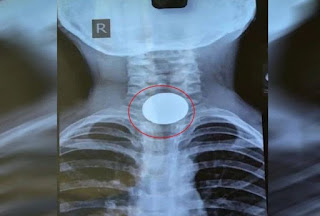

ऋषिकेश I उत्तराखंड में साढ़े पांच साल के बच्चे के गले में फंसे 10 रुपये के सिक्के को एम्स के चिकित्सकों ने बाहर निकाला। ज्वालापुर हरिद्वार निवासी साढ़े पांच साल के बच्चे ने खेलते समय 10 रुपये का सिक्का निगल लिया जो उसकी आहार नली में जाकर फंस गया।

इसके बाद बच्चे को बेचैनी होने लगी और वह चिल्लाने लगा। परिजनों ने उसे करीब ढाई घंटे के अंतराल में एम्स में भर्ती कराया। संस्थान के पीडियाट्रिक सर्जरी विभाग की टीम ने एनेस्थिसिया टीम की सहायता से ऑपरेशन थियेटर में फोलिस कैथेटर (गुब्बारे से युक्त रबड़ के पाइप के उपकरण) की सहायता से बच्चे की आहार नली में फंसे सिक्के को बाहर निकाला।

पीडियाट्रिक सर्जरी विभाग की डॉ. इनोनो यहोशु व डॉ. मनीष कुमार गुप्ता ने बताया कि फोलिस कैथेटर को बच्चे की नाक के रास्ते आहार नाल में फंसे सिक्के के नीचे तक डाला गया। इसके बाद सुई के जरिये पाइप में पानी भरकर गुब्बारे को फुलाया गया।

पाइप को धीरे- धीरे ऊपर खींचकर सिक्के के साथ बाहर निकाला गया। टीम में बाल शल्य चिकित्सा विभाग के डॉ. ज्ञानेंद्र, डॉ. नताशा, एनेस्थिसिया विभागाध्यक्ष डॉ. संजय अग्रवाल, डॉ. सीतू चौधरी, डॉ. देविथा आदि शामिल थे।